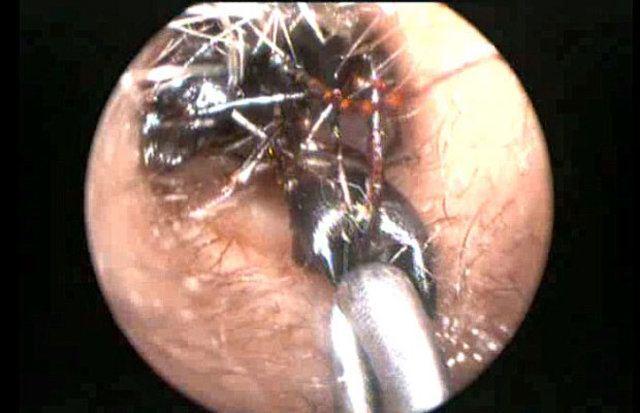

Kulağından binlercesi çıktı!

Shreya ilk kez geçen yılın Ağustos ayında sorun yaşamaya başladı. Kulak ağrısı şikayetiyle hastaneye götürülen küçük kızın kulak kanalında doktorlar karıncalar bulduğunu söyledi.